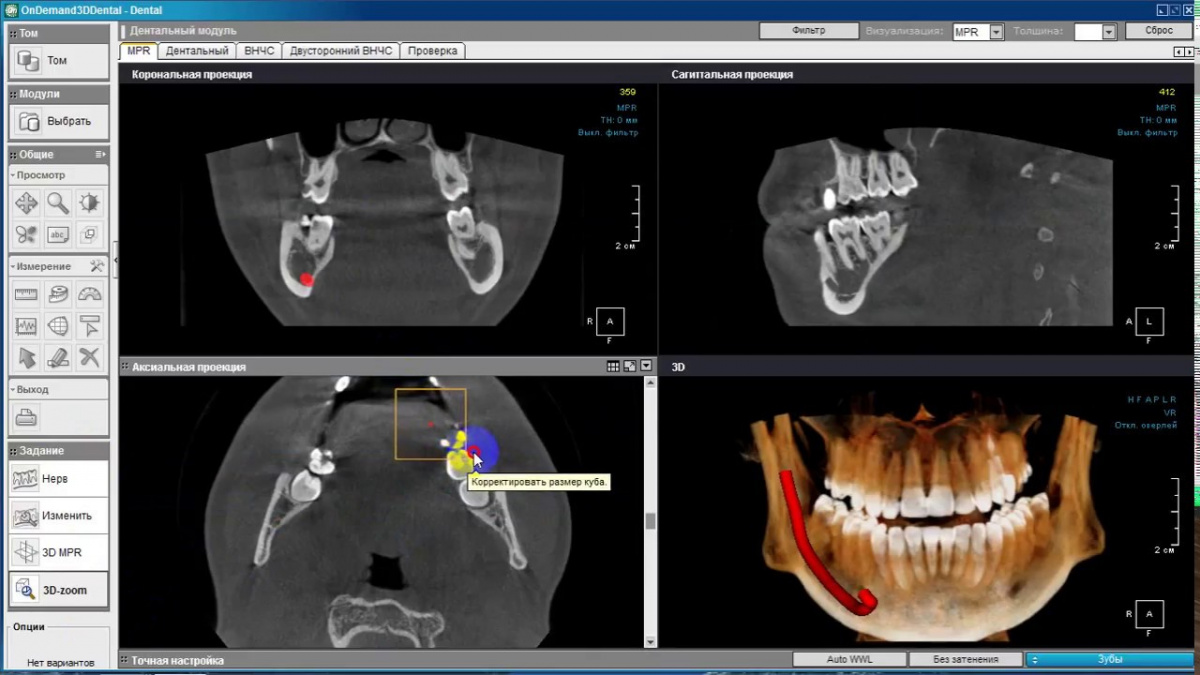

Немаловажным, а может главным вопросом, является универсальность программы-просмотровщика, в которой будут работать врачи-стоматологи. У Papaya 3D есть два варианта программ: Triana и OnDemand3D. Оба просмотровщика обладают схожим интерфейсом и имеют самые важные опции, а именно:

Таким образом обе программы являются простыми в пользовании, но обладающими обширным спектром возможностей для диагностики любыми специалистами-стоматологами. В данные программы происходит загрузка классических файлов DICOM 3.0, которые являются общепринятым форматом записи данных пациента. Это важный момент, так как позволяют врачу, имеющему полную версию программы загружать даже сторонние исследования и просматривать их в этих программах. Простота в освоении этих программ позволяет даже специалисту, не работающему раннее с этими программами, быстро адаптироваться и получить качественную информацию. Возможность выгрузки STL-файла дополнительно создает возможность интегрировать данные с цифровым ортопедическим протоколом.